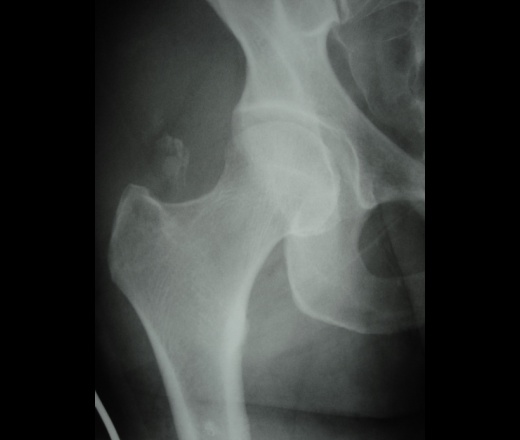

молодая женщина, спрыгнула со второго этажа при пожаре. Справа клиника ушиба, разможжение тканей, рваная рана бедра. травматологи написали отрывной перелом бедренной кости, в этом месте вижу впервые.

Отрывной перелом части большого вертела.

слева на вертеле тоже есть участок просветления. как эти кусочки поднялись так высоко, там же мышцы???

на счет большого вертела, похоже что да....

Разве там нечему тянуть?????